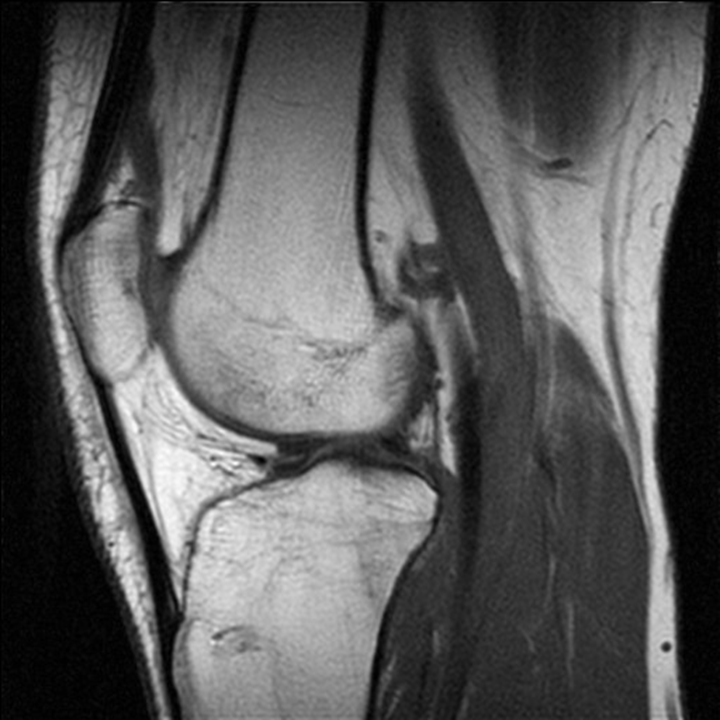

СУГЛОБ СКЛАДНИЙ. СУГЛОБОВА КАПСУЛА ТОНКА, УТВОРЮЄ БАГАТО СУМОК, ЯКІ СПОЛУЧАЮТЬСЯ ІЗ СУГЛОБОВОЮ ПОРОЖНИНОЮ. ЦЕ СПРИЯЄ ПЕРЕХОДУ ЗАПАЛЬНИХ ПРОЦЕСІВ (Є ДІАГНОЗ: БУРСИТ). ДЕ ВИ БАЧИТЕ ЦЕЙ СУГЛОБ.

варіанти відповідей

Запитання 51

РОЗПІЗНАЙТЕ СУГЛОБ, ЯКИЙ ЗАБЕЗПЕЧУЄ РУХИ ГОМІЛКИ.

Запитання 52

РОЗПІЗНАЙТЕ СКЛАДНИЙ СУГЛОБ, ЯКИЙ СКЛАДАЄТЬСЯ З ТРЬОХ КІСТОК, ОДНА З ЯКИХ РОЗТАШОВАНА В СУХОЖИЛКУ ЧОТИРИГОЛОВОГО М'ЯЗА СТЕГНА.

Запитання 59

СУГЛОБ СКЛАДНИЙ. УТВОРЕНИЙ СУГЛОБОВИМИ ПОВЕРХНЯМИ МЕДІАЛЬНОГО І ЛАТЕРАЛЬНОГО ВИРОСТКІВ, ЯКІ Є В ОБОХ КІСТКАХ, ЩО ЙОГО УТВОРЮЮТЬ. РОЗПІЗНАЙТЕ СУГЛОБ.

КОЛІННИЙ С.

ЛІКТЬОВИЙ С.

ГОМІЛКОВО--СТОПНИЙ С.

ПРОМЕНЕВО-ЗАП'ЯСТКОВИЙ С.